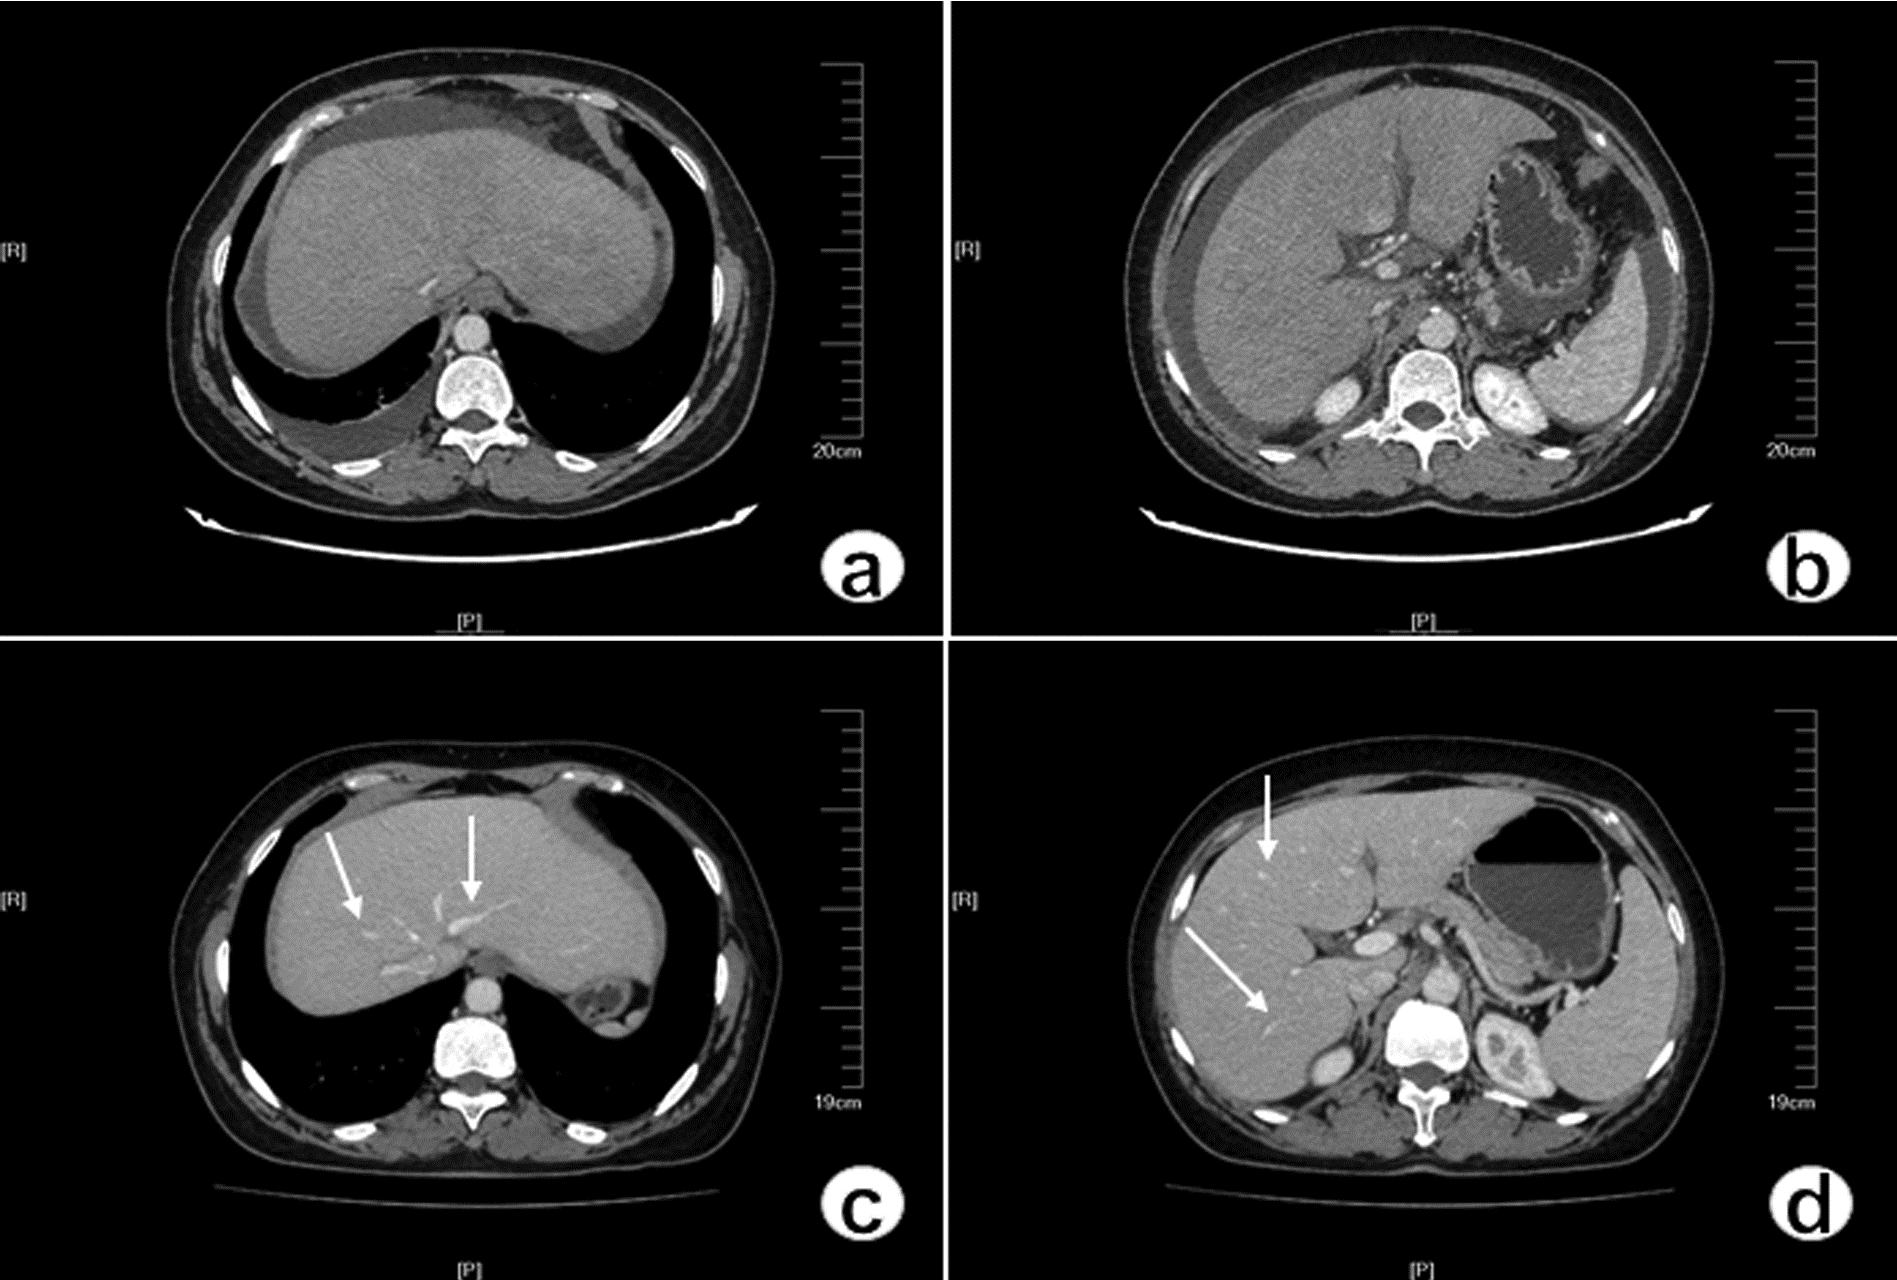

肝窦阻塞综合征成功诊治1例报告

耿雯倩, 朱浩, 杨鑫, 李婉玉, 许芳, 蔡艳俊, 高普均

2023, 39(2): 397-400. DOI: 10.3969/j.issn.1001-5256.2023.02.023

摘要(1461) HTML (477) PDF (2418KB)(136)

摘要: